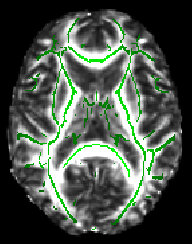

The -dr option sets sensible display range options, and in the case of the skeleton image, also controls the thresholding applied. Now turn on the movie loop; you will see the mean FA skeleton on top of each different subject's aligned FA image. If all the processing so far has worked ok the skeleton should look like the examples shown here (see the TBSS paper for more examples of different subjects' results underneath the skeleton). If the registration has worked well you should see that in general each subject's major tracts are reasonably well aligned to the relevant parts of the skeleton. If you set the skeleton threshold (in FSLeyes, the lower of the display range settings) much lower than 0.2, it will extend away towards extremes where there is too much cross-subject variability and where the nonlinear registration has not been able to attain good alignments. Remember the skeleton threshold for the next stage.